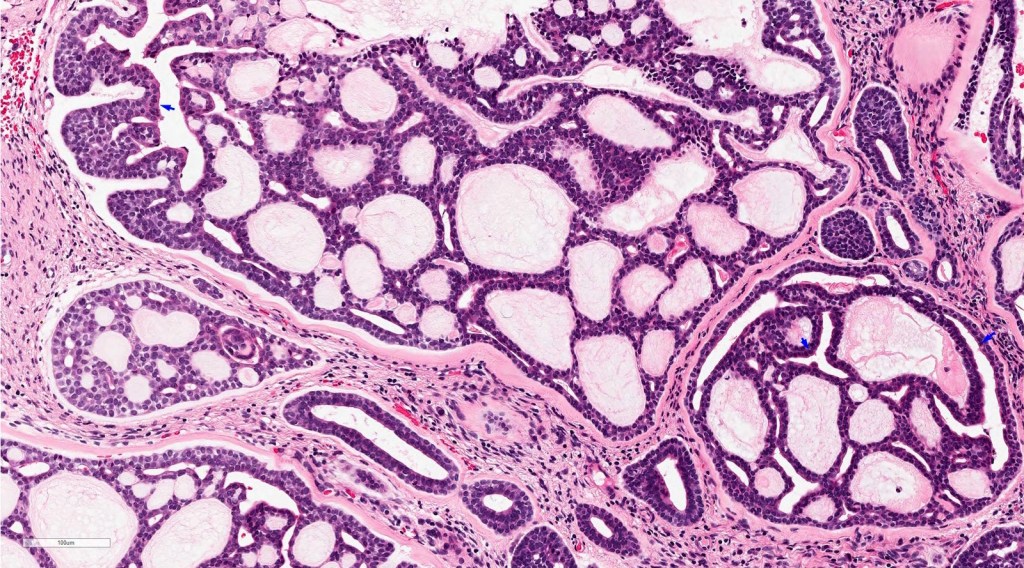

When a tooth fails to erupt properly, sometimes a cyst can form around it. This cyst is called a dentigerous cyst. It is characterized by a fibrous capsule, which is like a protective layer, and it is lined by stratified squamous epithelium, which is a type of tissue that forms the outer layer of the cyst.

Histologically, dentigerous cysts may show various features such as the thickness of the epithelial lining or the presence of inflammation or keratinization. However, these features are not unique to dentigerous cysts and can also be seen in other types of cysts.

A cyst was removed along with an unerupted third molar tooth. The pathologist reported a fibrous capsule that was myxoid in places and that was lined by a thin layer of squamous and cuboidal epithelium. The cyst originated from the amelocemental junction.